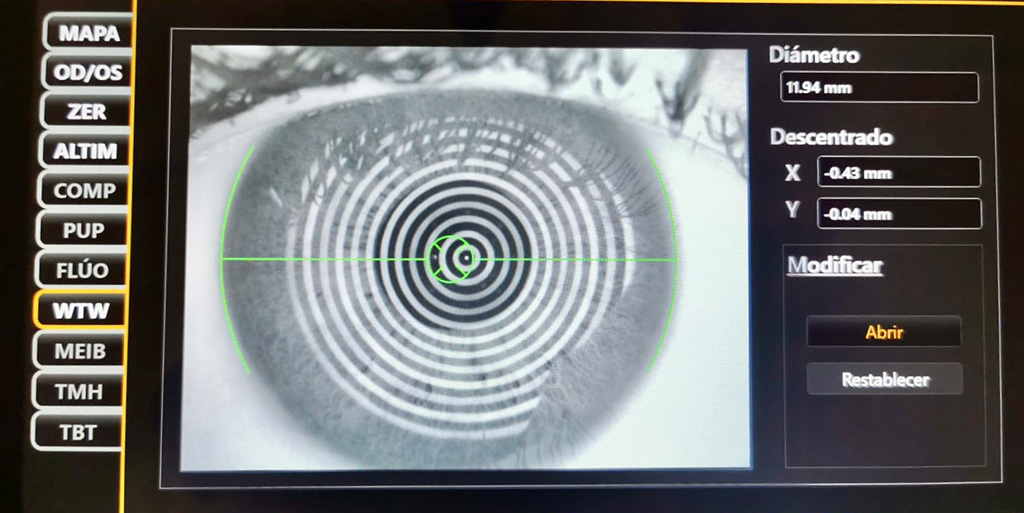

Biometría de última generación

es una técnica avanzada que mide con alta precisión las estructuras del ojo, como la longitud axial y la curvatura corneal. Esto permite seleccionar la lente intraocular ideal para cada paciente, optimizando la visión tanto de lejos como de cerca tras la cirugía de catarata y corrigiendo, si se desea, la presbicia.